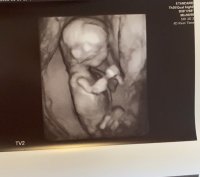

I dag har vi hilset på en frisk og fin liten lillebror :Heartblue ble satt frem en dag, så er 13+6 i dag :)

Ny tidlig ultralyd i dag, 13+6. Vi fikk vite at vi venter en liten gutt! :Heartblue :joyful: